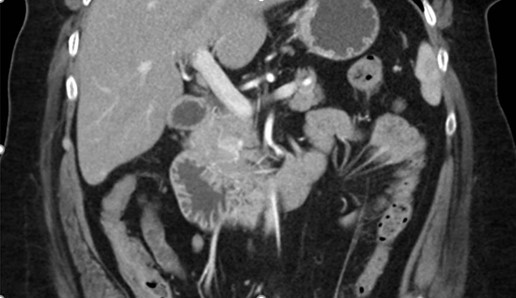

Tomografía de abdomen y pelvis con cte ev: del 13/10/2023.

Complicaciones posquirúrgicas

Tomografía de abdomen con cte ev: del 20/10/2023.